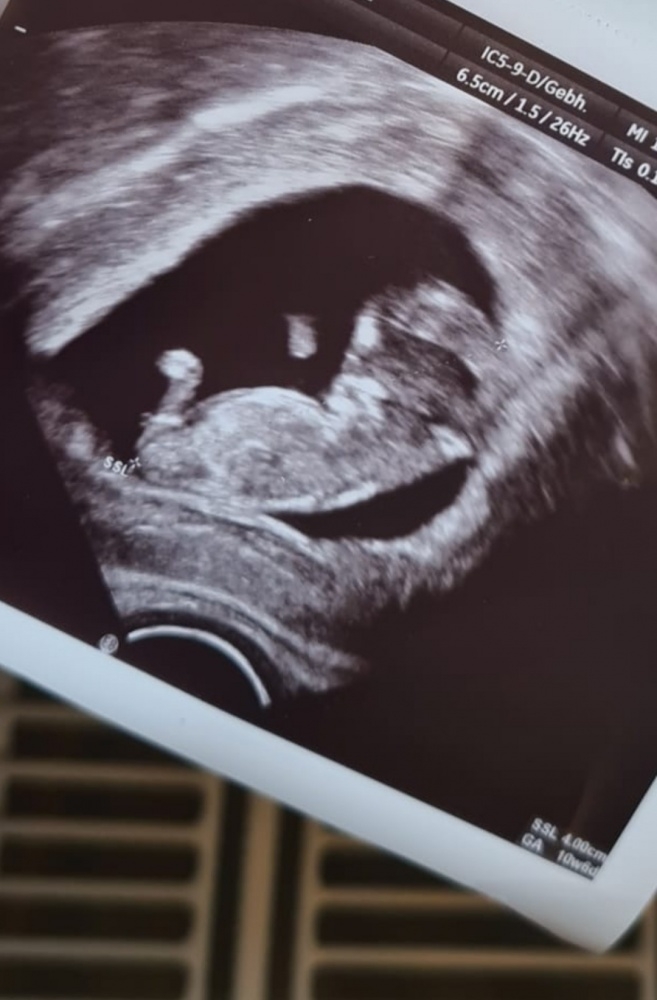

Also ich kann euch ja gerne noch mal mein Ultraschall Bild zum Vergleich

reinschicken, was ich damals vom Krankenhaus bekommen habe. Habe ein Mädchen bekommen und das sah man am Bild recht deutlich laut Nub Thorie. Müsste so ungefähr in der 16. Woche gewesen sein aber meine Fa hats mir erst in der 22. Woche gesagt